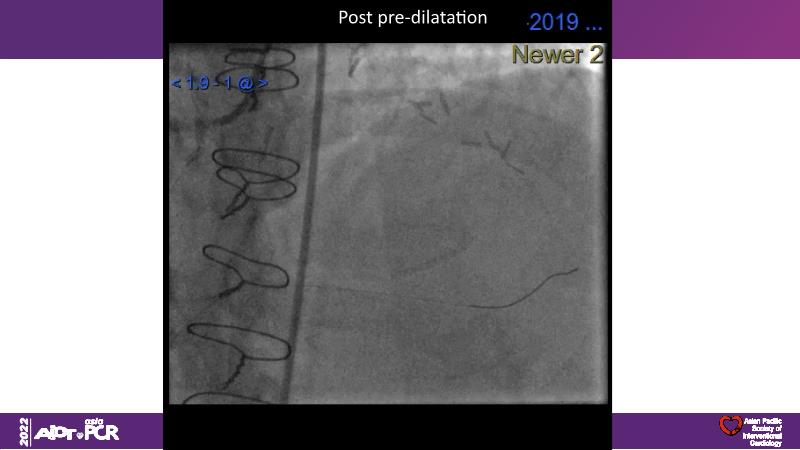

Consult this session to understand the technology and scientific evidence of the novel sirolimus drug-coated balloon, to learn its utility for PCI in a variety of lesion and patient subsets and to understand the evidence and outcomes in real-world patients.

- To learn the utility of the DCB for PCI in a variety of lesion and patient subsets